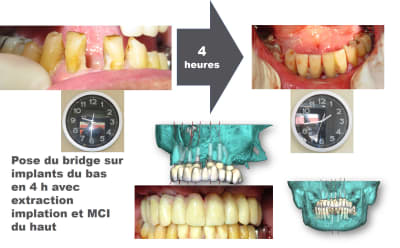

Pour conclure avec ce cas qui n'a suscité aucun commentaire, voici celui qui accompagnait

la vidéo d'où sont extraites les photos : "Affaire du jour. Une partie du cours de protho commence dans 2 semaines. Apprenez à simplifier les cas d'implant en arche complète de façon prévisible.

Concept star inspiré par..."

Son auteur propose une formation de simplification en réhabilitation totale de maxillaire en prothèse implanto-portée e présentant un cas qui démarre avec 11% d'échec implantaire.

Autrement voici le prochain cas de pluton

Pourquoi remettre au lendemain ce qui peut être fait en 3 heures ?